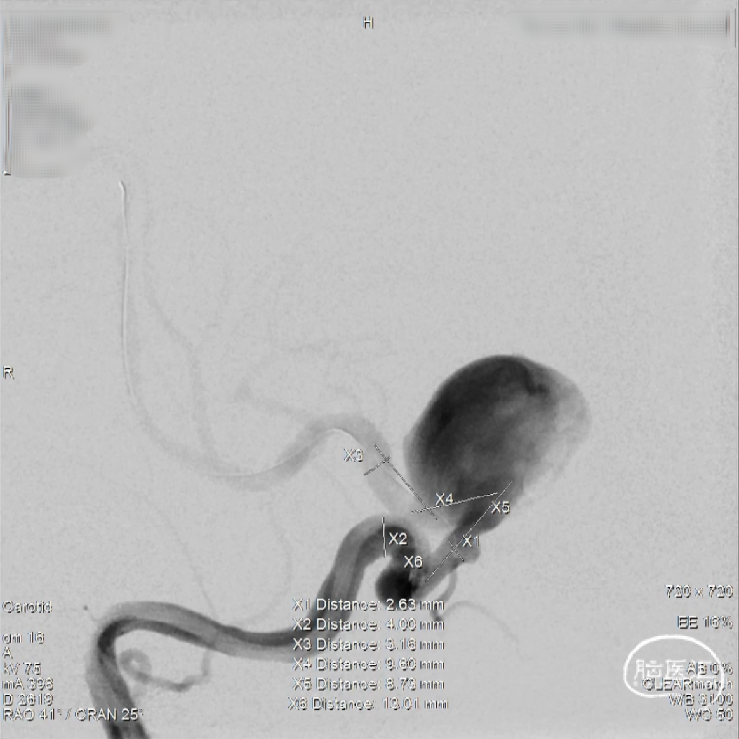

Step8:术后即刻工作位造影,可见瘤颈部位及囊内血流滞留明显,支架打开、贴壁良好。

术后检查

术后即刻正侧位造影,动脉瘤滞留明显、远端血流通畅。